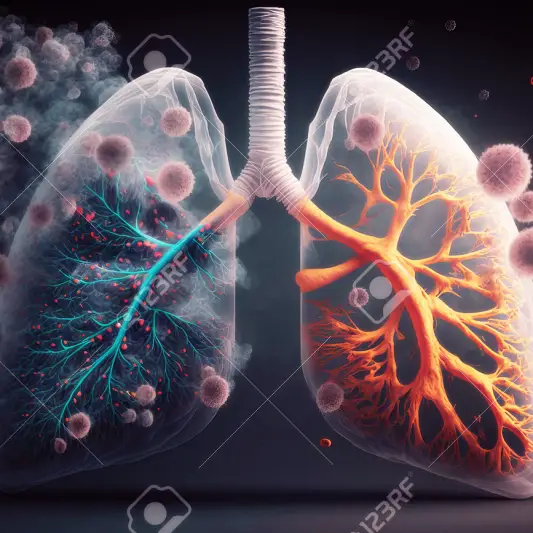

식단 조절 및 영양 섭취

폐암 수술은 환자의 건강을 회복시키기 위한 중요한 과정입니다. 하지만 수술 후에는 적절한 관리와 영양 섭취가 필요합니다. 식단을 조절하고 영양을 적절히 섭취함으로써 회복 속도와 건강 상태를 개선할 수 있습니다.

폐암 수술 후 필요한 관리와 영양 섭취의 중요성은 막연한 것이 아닙니다. 적절한 식단과 영양 섭취를 통해 환자의 회복 속도와 건강 상태를 개선할 수 있습니다. 수술 후 올바른 식사와 관리를 통해 환자는 빠른 시간 안에 삶의 질을 회복할 수 있습니다.활동 수준 조절 및 운동